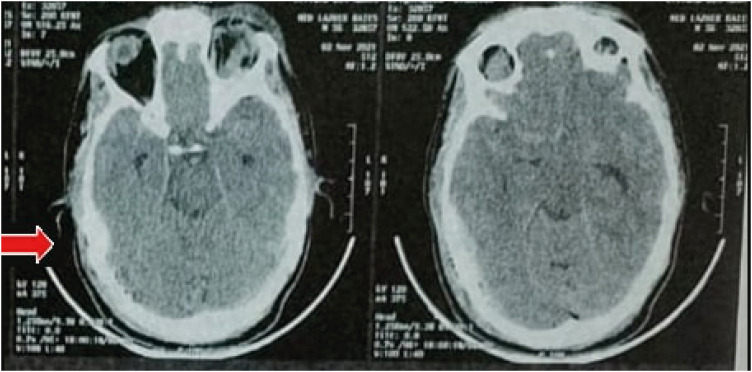

Abstract Image